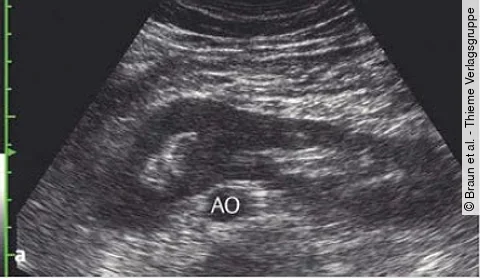

Uro-Quiz der Woche: Hufeisenniere mit weiterer AuffälligkeitBraun et al. - Thieme VerlagsgruppeLassen Sie sich nicht von dieser angeborenen Fehlbildung irreleiten.